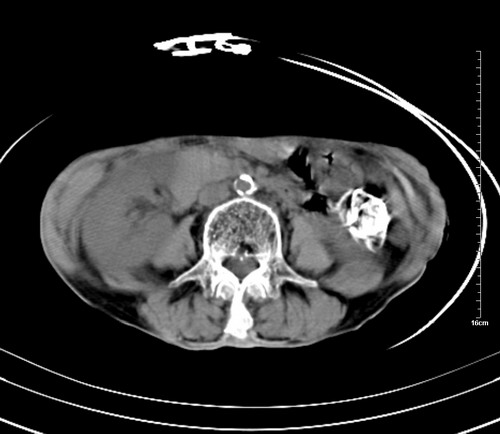

病人,女,79岁,主要因腹疼二月入院,彩超,肝,胆,脾,未见异常,胸透上消化道造影未见异常,化验白细胞增高,内科医生让做胸部ct检查,因为熟人多做了腹部(外科会诊考虑胆囊炎).现ct片如下请假各位战友.

1 气管旁、隆突下淋巴结明显肿大,肝左叶外侧段低密影,都考虑转移。

2 肝右后叶下段明显增大,片状低密影,但因各种伪影显示不佳,不排除病变。

后中纵隔团块影,伴气管、食道受压移位,首先考虑转移瘤,肝s5段低密度灶。建议增强检查,另外其结肠是否有问题请提供,右肺部分肺叶局限含气增多,考虑局限肺气肿。

后中纵隔团块影,伴气管、食道受压移位,首先考虑转移瘤,肝表现同11773。